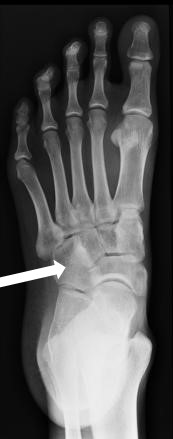

Którą kość zaznaczono strzałką na radiogramie stopy?

A. Kość łódkowatą.

B. Kość klinowatą boczną.

C. Kość sześcienną.

D. Kość skokową.